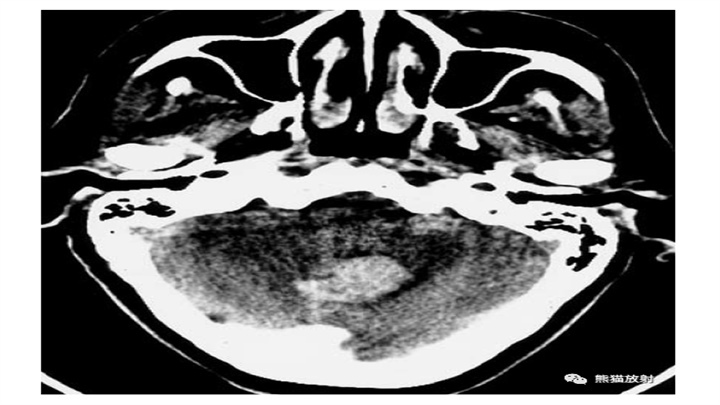

8岁女孩突然昏迷。小脑IPH伴蛛网膜下腔出血,脑干缺血性密度减低,脑积水(侧脑室颞角扩大)。小脑蚓部是“隐性血管瘤”最常见的部位之一。